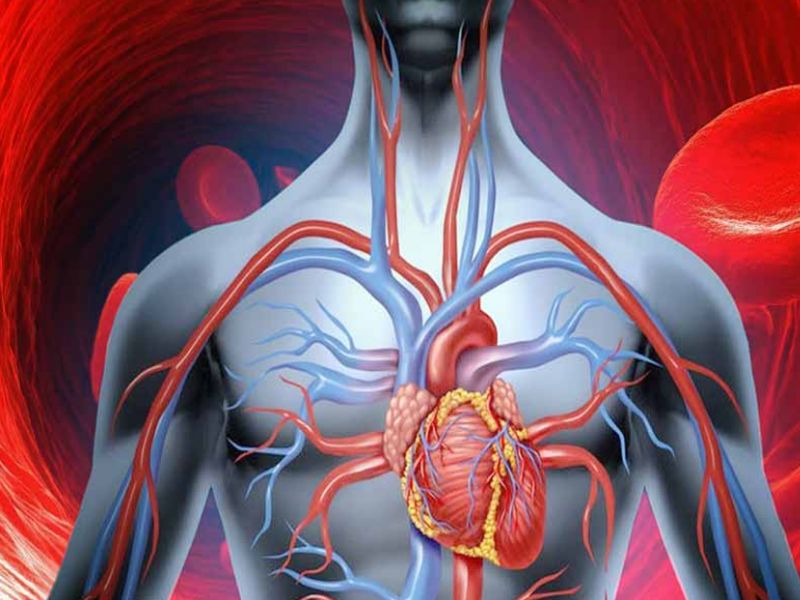

इव हिंदी खबर (हेल्थ टिप्स ) :- हार्ट अटैक को बुजुर्गों की बीमारी माना जाता है और धनवानों के दिल की धड़कन की कार्यवाही इस वर्ग से होती है। लेकिन मौजूदा समय के भयानक जीवन-शैली और खाने के कारण, कोरोनरी हार्ट अटैक की इस बीमारी ने हर व्यक्ति को अपना शिकार बनाना शुरू कर दिया है। यह कहा जाता है कि अचानक दिल का दौरा पड़ने वाले व्यक्ति में कोई ऐसा व्यक्ति शामिल होता है जिसे कोई भी व्यक्ति महसूस नहीं कर सकता है। लेकिन यह हमेशा ऐसा नहीं होता है जब वह कोरोनरी हार्ट अटैक से पहले लक्षण और लक्षण प्राप्त करना शुरू कर देता है। आज हम आपको कोरोनरी हार्ट अटैक से पहले के लक्षणों और लक्षणों से अवगत कराने जा रहे हैं ताकि आप उन्हें महसूस कर सकें और यदि आप कभी भी इस प्रकार की समस्या का सामना करते हैं, तो आप पहले से सतर्क हो सकते हैं। इसलिए हमें कोरोनरी हार्ट अटैक की तुलना में पहले लक्षण और लक्षणों का एहसास करने की अनुमति दें।